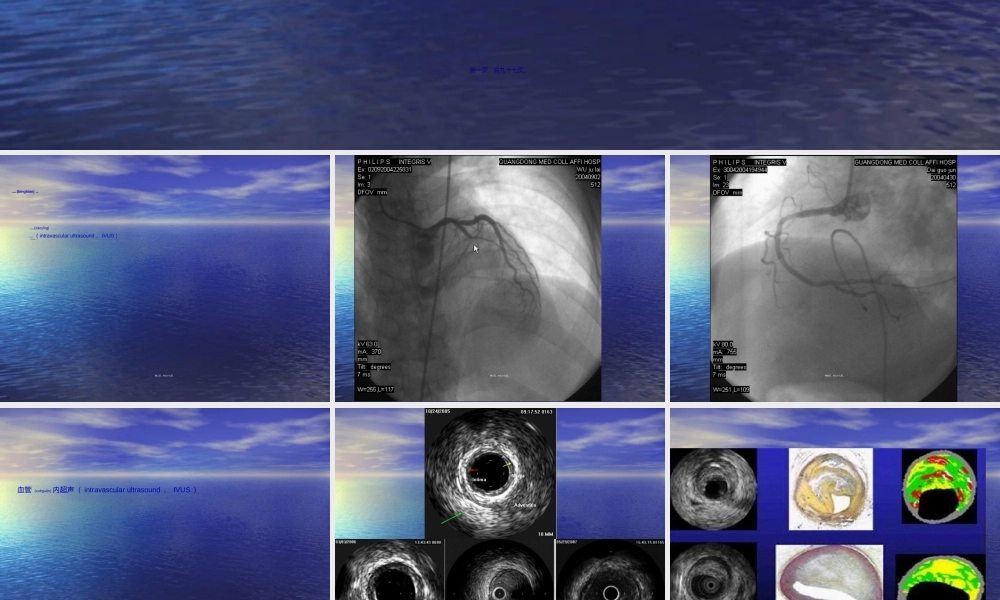

6464排螺旋排螺旋(luóxuán)(luóxuán)CTCT的冠状动脉的冠状动脉成像成像第一页,共九十七页。冠状动脉病变(bìngbiàn)的显示:•冠状动脉造影(zàoyǐng)(coronaryangiogram)•血管内超声(intravascularultrasound,IVUS)•CT冠状动脉成像(CTCA)第二页,共九十七页。第三页,共九十七页。第四页,共九十七页。血管(xuèguǎn)内超声(intravascularultrasound,IVUS)第五页,共九十七页。第六页,共九十七页。第七页,共九十七页。CT冠状动脉(guānzhuàng-dòngmài)成像(CTCA)第八页,共九十七页。第九页,共九十七页。第十页,共九十七页。第十一页,共九十七页。第十二页,共九十七页。CT在冠状动脉病变诊断(zhěnduàn)上的发展•电子束CT(electronbeamcomputedtomography,EBCT)•多排螺旋(luóxuán)CT(MSCT)第十三页,共九十七页。二、冠状动脉(guānzhuàng-dòngmài)的解剖:•冠状动脉是供应心肌血、氧的血管,它的解剖形态颇多变异。在正常情况下冠状动脉有左、右两支,分别开口于升主动脉的左、右冠状动脉瓣窦,有时(yǒushí)从主动脉发出另一支较小的副冠状动脉。第十四页,共九十七页。第十五页,共九十七页。第十六页,共九十七页。第十七页,共九十七页。第十八页,共九十七页。第十九页,共九十七页。冠状动脉病变的定位可直接用各血管支的名称(míngchēng)外,可选用15段分法来描述。第二十页,共九十七页。三、64排CT对冠状动脉病变(bìngbiàn)的诊断第二十一页,共九十七页。检查(jiǎnchá)方法:第二十二页,共九十七页。患者(huànzhě)应无对比剂使用禁忌,能屏气10秒以上。检查时心率应控制在90次/分以下(最好75次/分以下),无严重心率失常,必要时可使用药物控制。第二十三页,共九十七页。先行平扫(不使用对比剂),图像用于钙化积分分析(fēnxī)。增强时使用双筒高压注射器注射对比剂,注射流率4-5ml/s,因此,病人应的较好的外周静脉条件。第二十四页,共九十七页。第二十五页,共九十七页。对比剂最好采用(cǎiyòng)370g以上浓度非离子型对比剂。可采用(cǎiyòng)Bolustracking或TestBolus两种方式追踪最佳扫描时机。通常采用(cǎiyòng)后置心电门控,60-80%时相重建(PHILIPS推荐45%、75%双时相重建)。第二十六页,共九十七页。扫描时采用64x0.625探测器,0.8-1.0mm层厚重建原始图像。部分心率失常造成的图像质量不佳,可通过心电编辑(biānjí)技术进行修正。联合使用MIP、MPR、CPR、...